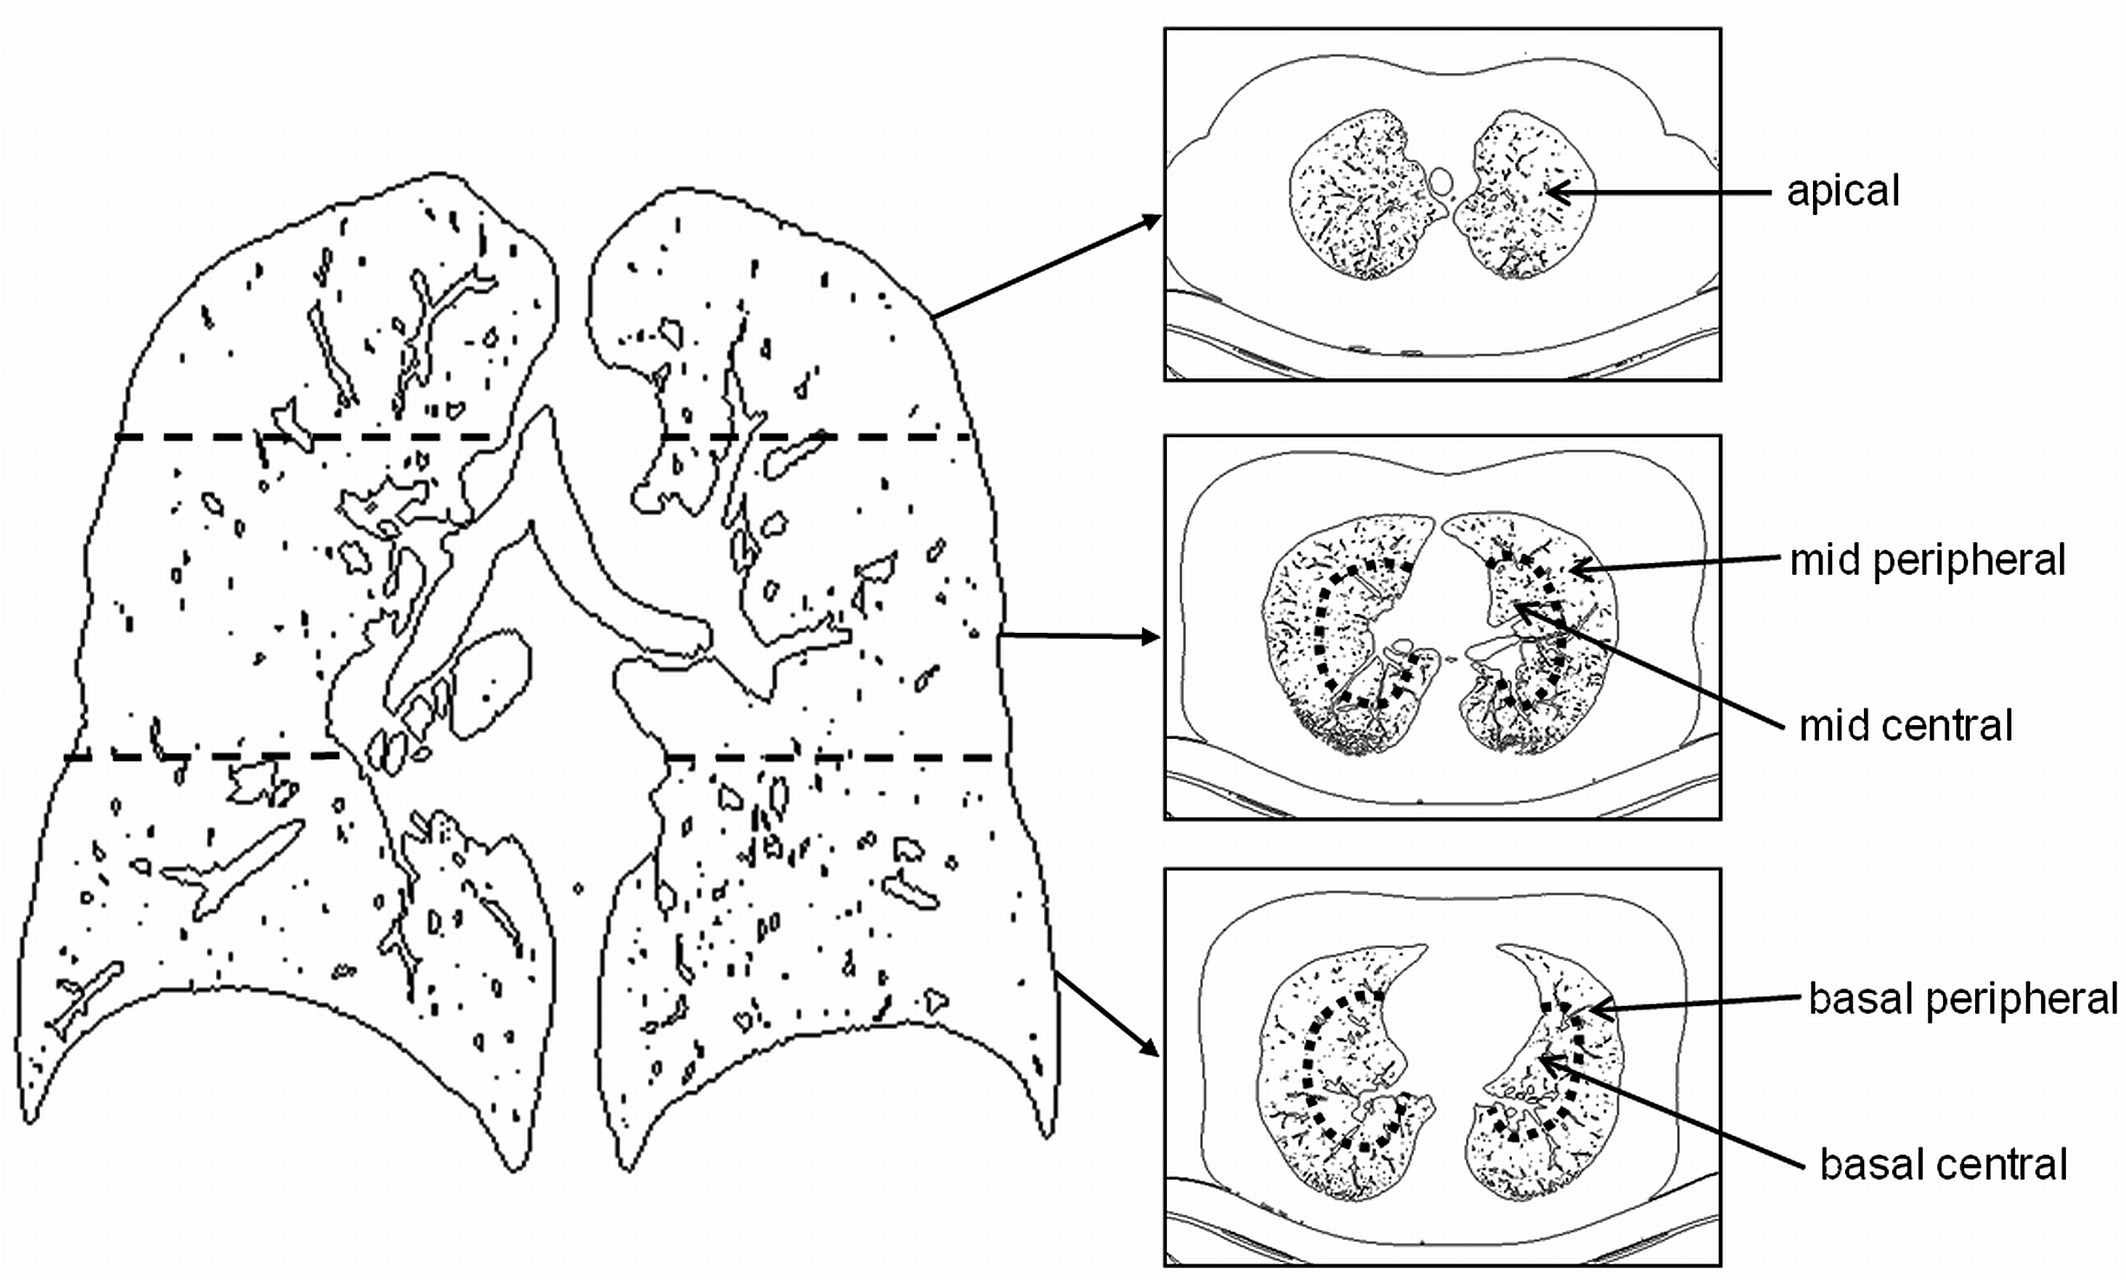

폐 위치 관련한 용어를 잠시 보여드리면 아래와 같습니다.

아래 사진을보면 정상인, 폐렴, COVID-19 의 폐 CT 사진입니다.

아래 사진을 기반으로 하면 다음과 같이 해부학적으로 병변을 분류할 수 있겠죠.

- Normal: 깨끗함

- Pneumonia: 광범위하게 GGO(Ground Glass Opacity)가 퍼져있음

- COVID-19: peripheral부분에 GGO가 위치하기도 하며, 진행단계에 따라 GGO 정도가 심해지는 consolidation 현상도 볼 수 있습니다.